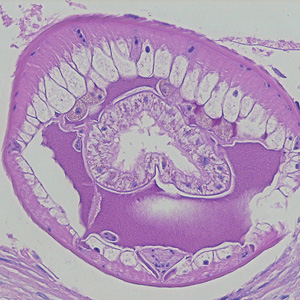

A huntsman killed a bear and prepared it for eating and freezing by cutting it into roasts, steaks, and grinding the trimmings. Later that same day, he ate a burger made from some of the fresh meat and cooked rare. Approximately two and a half to three weeks later, the hunter experienced fever, diarrhea, and muscle pain.